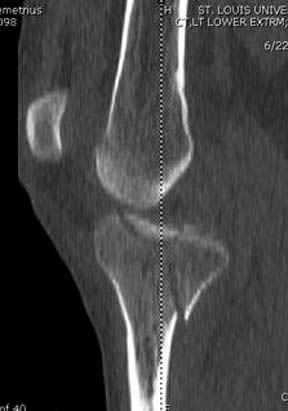

Пациенту сделали КТ - ухитрились сделать на шине Белера (не давал положить прямую ногу) - срезали передний отдел. Планируется на пятницу (24.12) на операцию - синтез длинной мыщелковой LCP-пластиной Synthes :). Отек ближе к слову умеренный (окружность голени +4 см по сравнению со здоровой). КТ и снимок на вытяжении прилагаются.

На представленных предоперационных срезах КТ огромный задне-медиальный фрагмент расположен больше кзади, чем медиально. Для планирования, кроме поперечных срезов, надо ориентироваться на корональные срезы, которые укажут топографию верхушки медиального фрагмента.